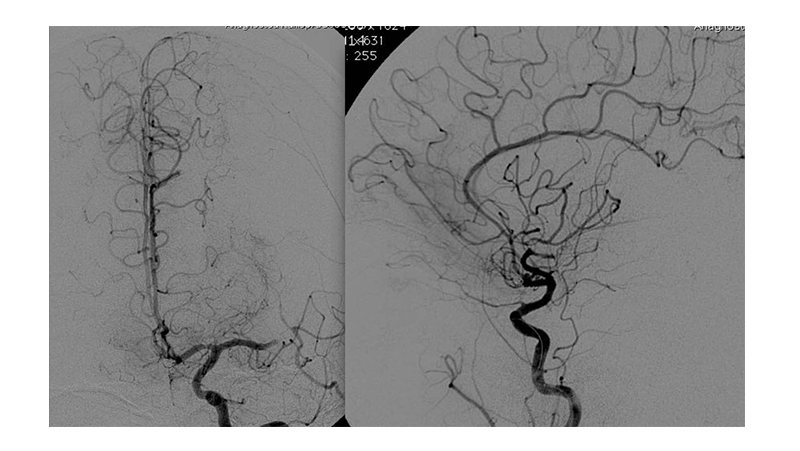

Εικόνα 3: Αγγειογραφία της αριστερής έσω καρωτίδος σε προσθιοπίσθια και πλάγια προβολή: Διακρίνεται η απόφραξη του τέλους του Μ1 τμήματος της μέσης εγκεφαλικής αρτηρίας.

Εικόνα 4: Διέλευση με μικροκαθετήρα της αποφράξεως και τοποθέτηση του μικροκαθετήρα στο βάθος του Μ2.